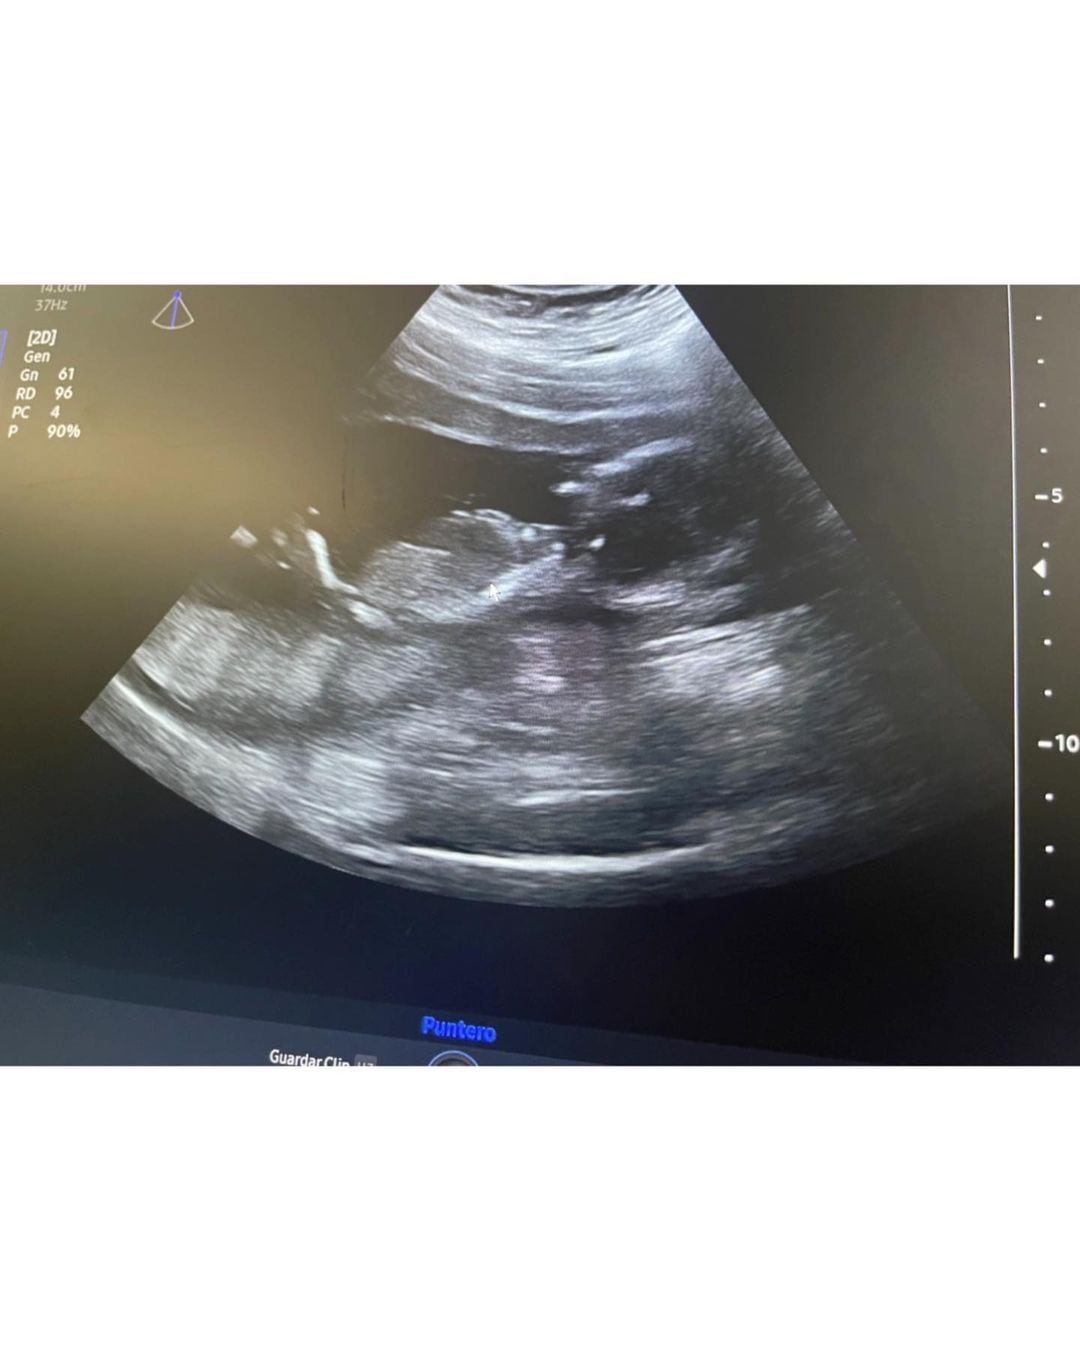

“No se por donde empezar. Lamentablemente hace unos días vengo pasando los peores días de mi vida, la pérdida de un embarazo es complicado de afrontar, de sobrellevar y poder asumir, más que nada cuando pensás que todo iba bien y de golpe todo se derrumba”, comenzó expresando junto a un video, en el que se ve como se movía su panza, y una foto de una ecografía que se había hecho recientemente. Y continuó: “Son momentos complicados, y pido el respeto que se merece cualquier persona que pasa por estas situaciones. Me esta costando muchísimo poder levantarme de esta, pero la vida tiene que continuar”. Por último, cerró dirigiéndose al bebé que estaba esperando: “Y a vos mi vida, que decirte. Estés donde estés, te voy a extrañar, todos los días”.

“Maxi me compró un test, me lo hice y me enteré ahí. Él es papá de una nena de 9 años, y yo de Fran, así que estamos re contentos”, había revelado en esa ocasión. En este punto Ángel de Brito aclaró cómo había surgido el rumor de la dulce espera: “Se hizo una ecografía hace muy poquito y obviamente la vieron en el lugar y nos llegó la información”.